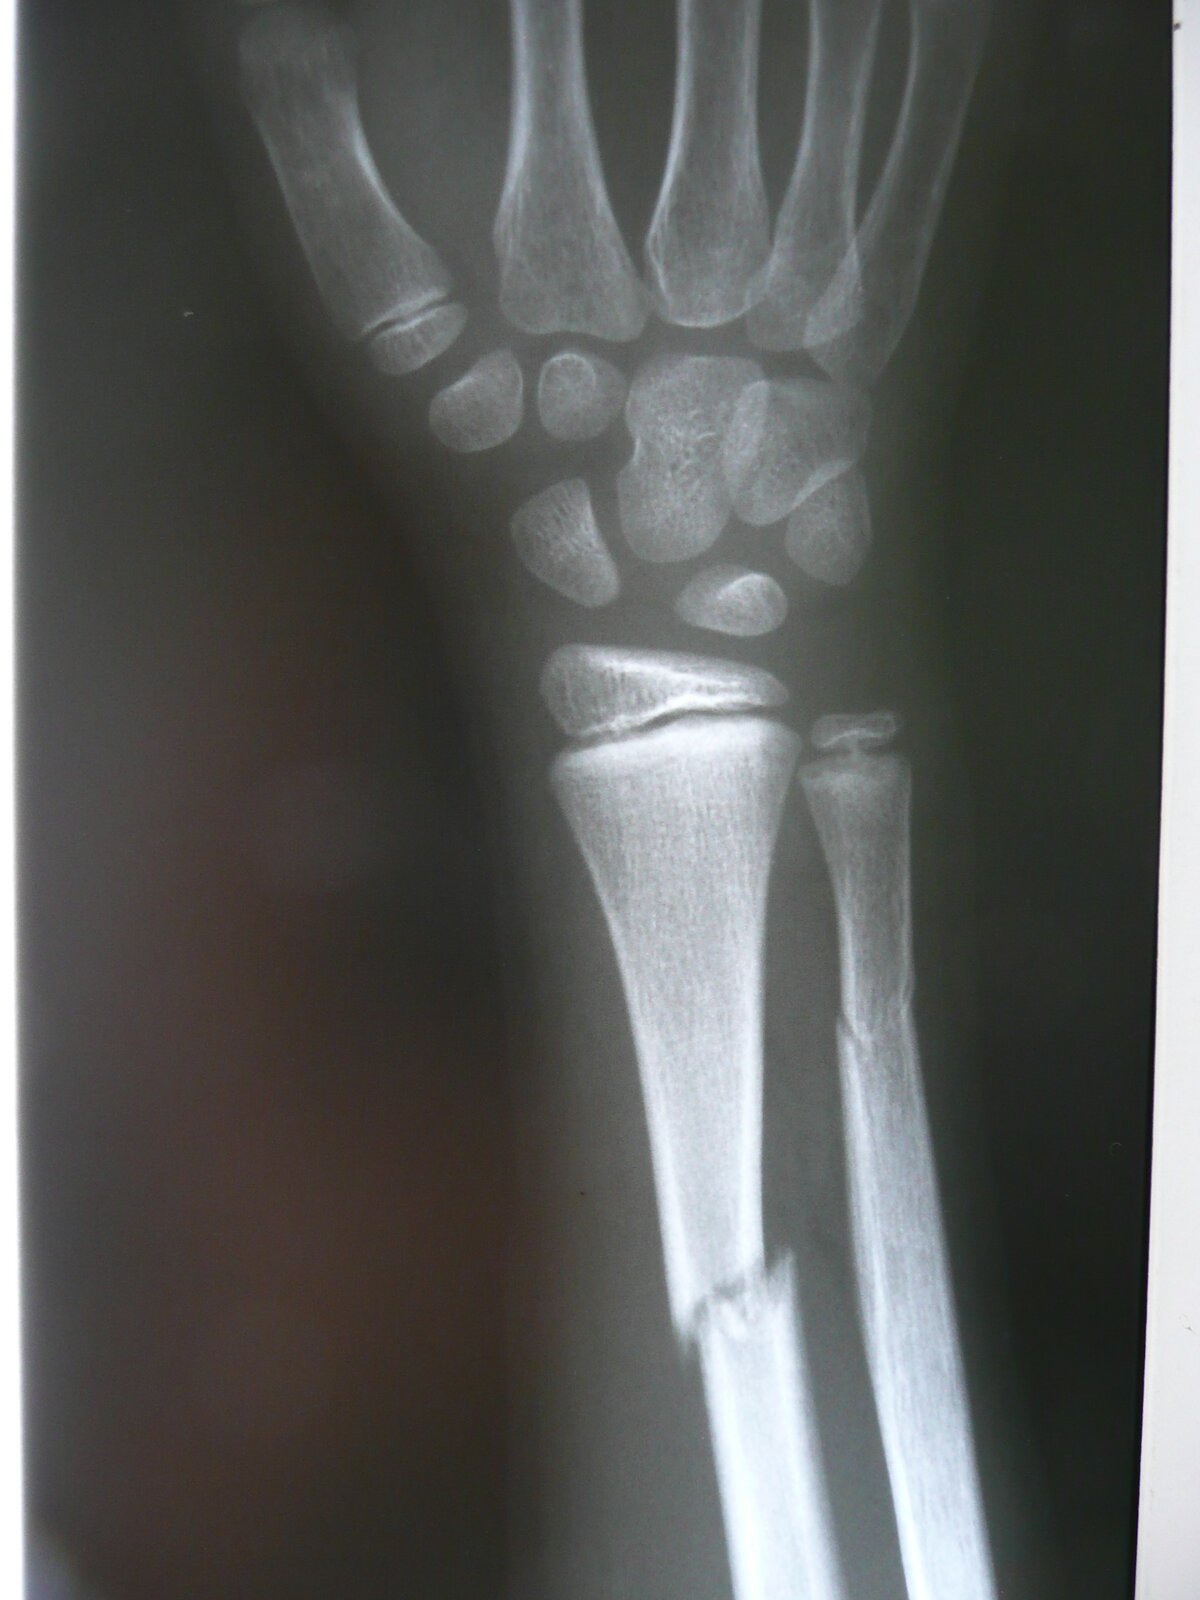

Każde odkrycie sytuuje się pomiędzy tymi skrajnościami. Wilhelm Roentgen, odkrywając promienie X był bardzo bliski tej drugiej skrajności. Warto poznać historię odkrycia, które parę miesięcy po dokonaniu dało lekarzom narzędzie diagnostyczne ich marzeń, …

a sześć lat później przyniosło autorowi nagrodę marzeń: pierwszą w dziejach nagrodę Nobla z fizyki.